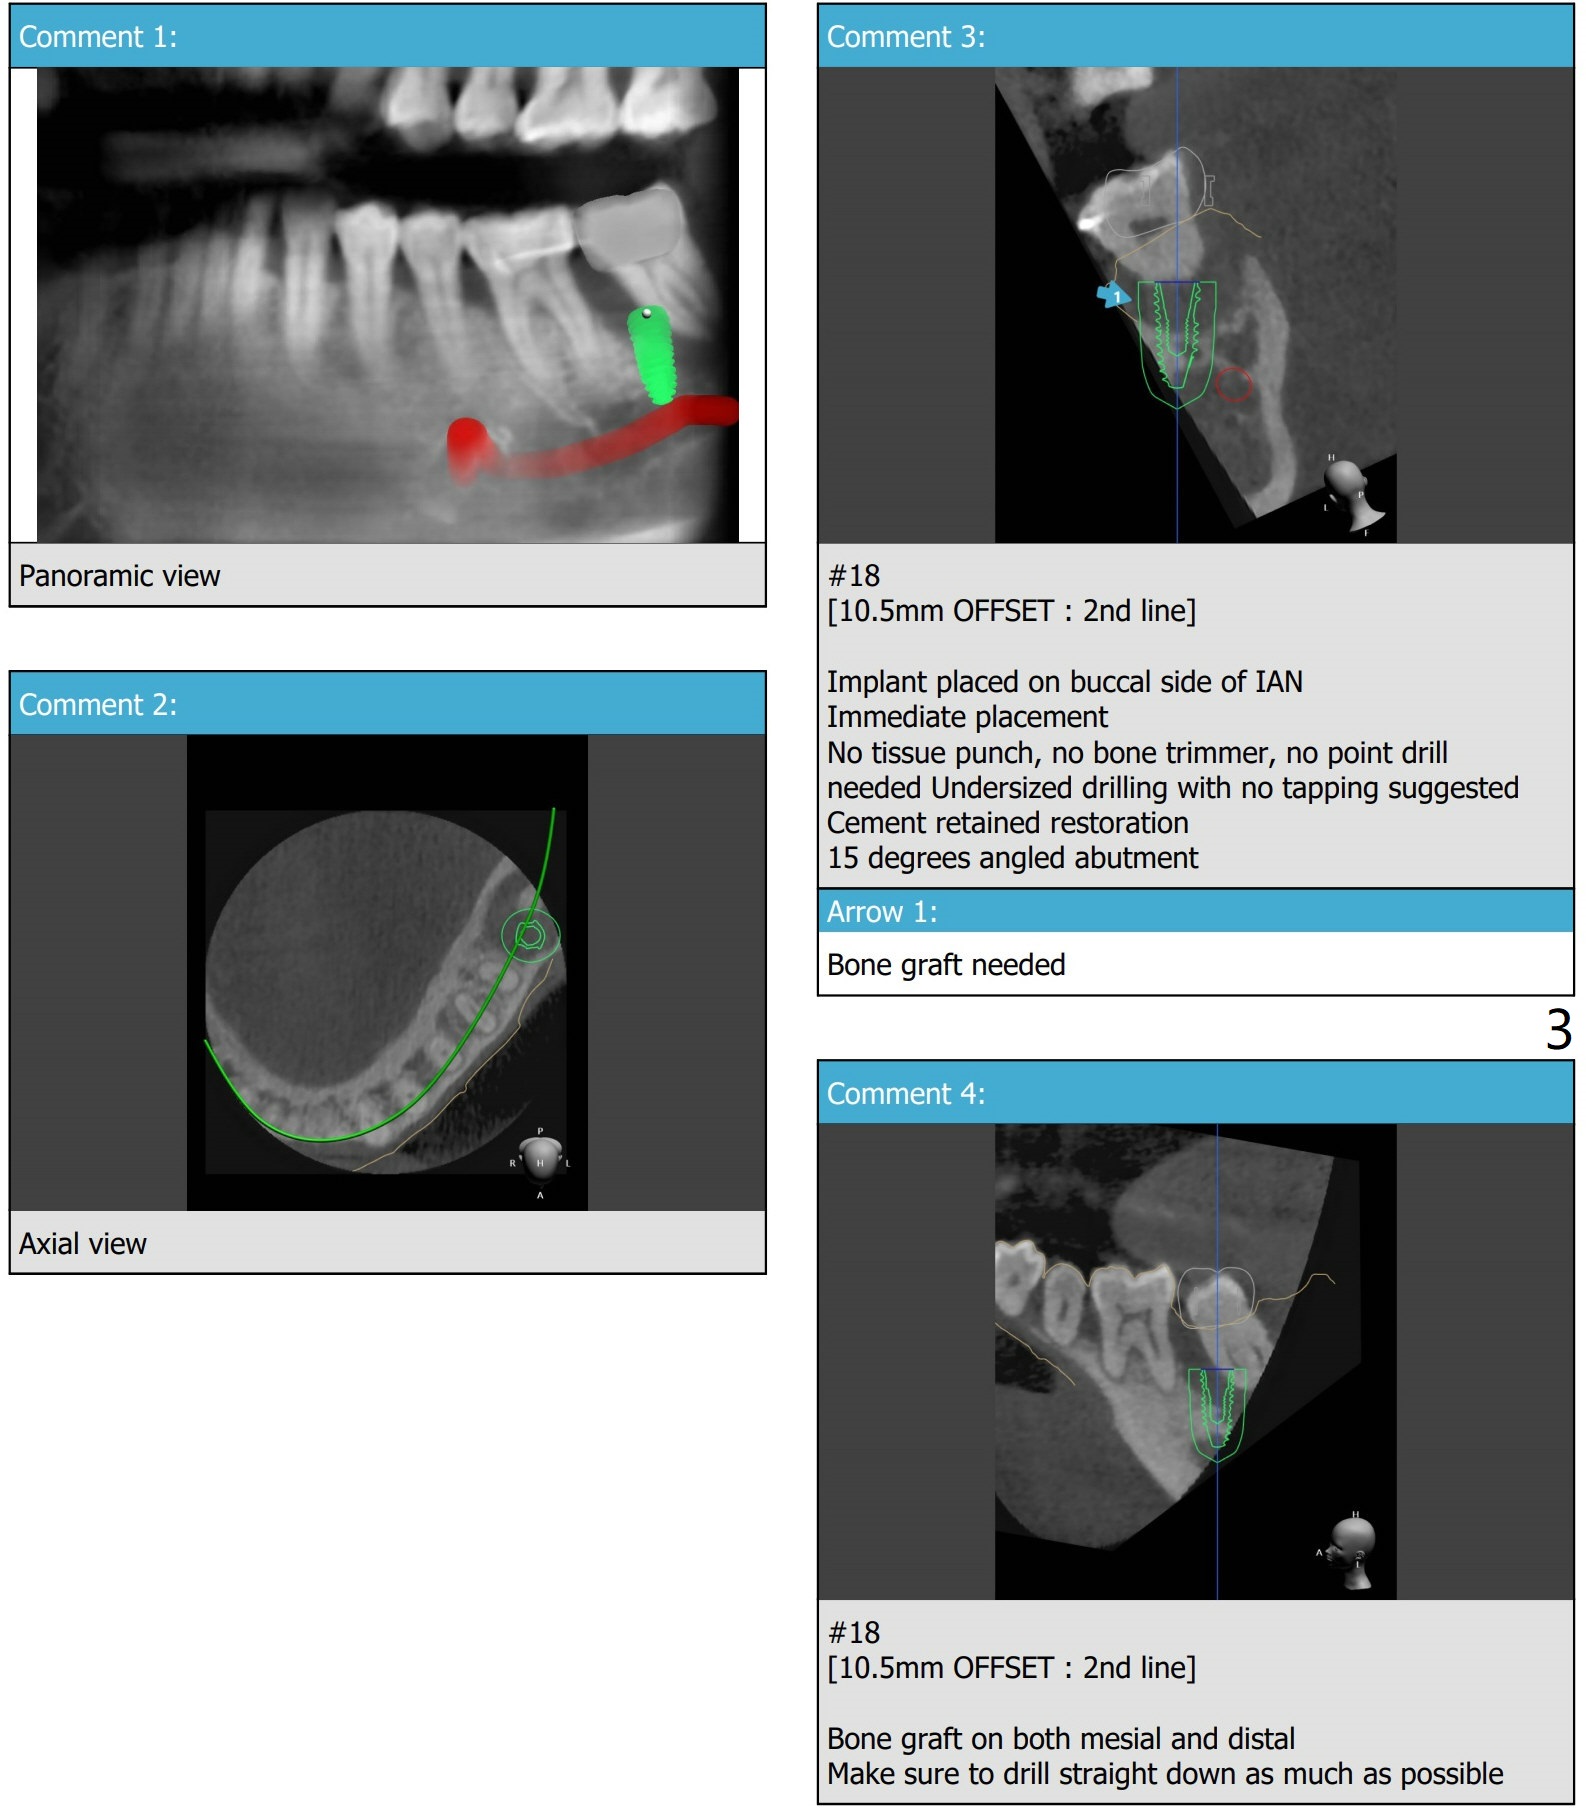

Bypass IAC/Angled Abutment